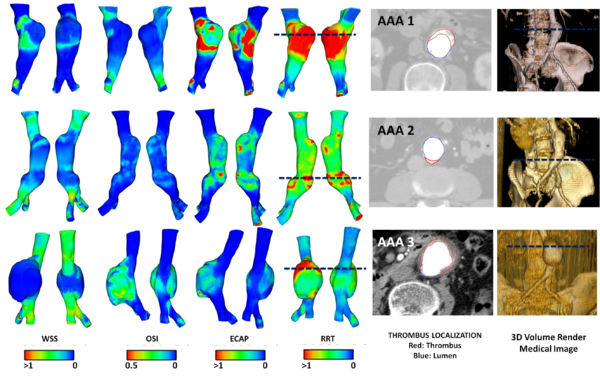

The hemodynamic variables for the thirteen abdominal aneurysms were obtained using image-based CFD under realistic flow conditions. The AAA simulations were performed for three cardiac cycles, and the results from the last cardiac cycle were used to compute the WSS-based diagnostic indicators (WSS(eq.1.2), OSI(eq.1.4), ECAP(eq.1.6) and RRT(eq.1.5)). Depending on the complexity of the AAA model, a 3D mesh consisted of 1.000.000 tetrahedral elements. A boundary layer was created to capture properly the velocities close to the wall. Next image shows the WSS, OSI, ECAP and RRT values for three different AAAs.

6.2.1 Conclusions

The computed WSS-based diagnostic indicators combined with the geometrical factors may provide more information about ILT development for a complex AAA geometries. The results show that aneurysmal wall regions with increased flow and high tortuosity index may be prone to thrombus deposition, and consequently, ILT formation. Higher values of the RRT and ECAP indices correspond to the areas with ILT, as is shown in figure 14. A preliminary analysis of the thirteen AAA confirmed that the length, asymmetry and saccular index significantly influence in the WSS-based diagnostic indicators, which highlight the weight of these variables on the ILT development and the rupture-prone AAA areas. No correlations between maximum diameter and WSS-based diagnostic indicators were obtained, as might be expected. This finding is in agreement with the strategy adopted in the research, all the AAAs considered have a diameter around 40 mm, and therefore the rupture risk is not significant. The study shows that WSS-based diagnostic indicators may provide important additional information on aneurysm progression on a patient-specific basis. Based on this preliminary study, it is possible to hypothesize that the characterization of AAA morphometry and its influence on the regional and temporal distribution of the hemodynamical variables would be necessary for patient-specific assessment of rupture risk and ILT development. To improve the reliability of the results, would be needed to expand the number of cases in the study. The methodology here developed could be an indicative that other indices like, asymmetry, deformation rate, AAA length, saccular index, are important and could also be readily incorporated into surgeon's decision making, instead of the classical maximum diameter criterion.